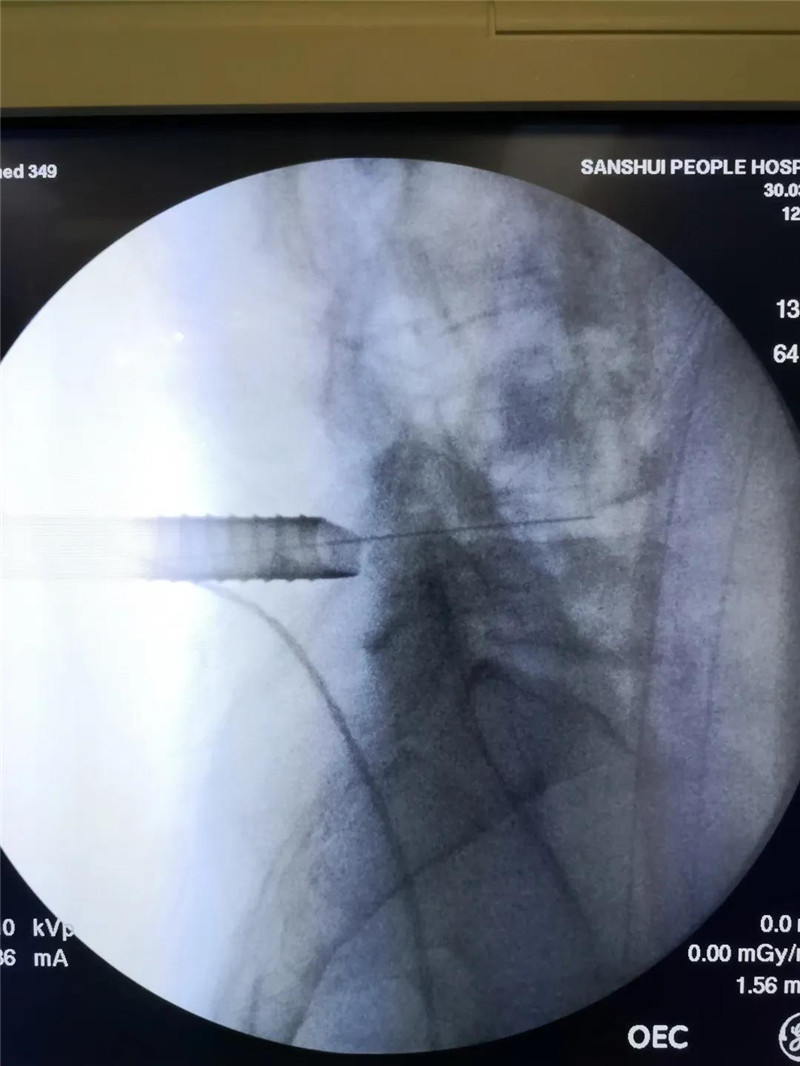

据罗先生介绍,7年前弯腰提重物时,腰部发出“咔”的一声,随即出现腰痛症状,休息后好转,近3年来症状反复发作,用尽各种理疗方法,不尽人意。近1周来患者腰痛加重,伴右下肢疼痛剧烈、麻木,步履艰难,彻夜难眠。于外院行针灸理疗等保守治疗,缓解不明显,严重影响生活质量。患者于2020-4-15入住脊柱关节外科,入院MRI示:腰4/5椎间盘突出并明显椎管狭窄,右侧神经根严重受压。17日由潘磊主任主刀,陈伟雄副主任医师、焦伟东医师协助下为患者实施腰后路经皮Delta通道孔镜下腰4/5髓核摘除+神经根粘连松解术,该术式术野更清晰,操作更安全方便。术后患者伤口愈合良好,术前腰痛、右下肢疼痛、麻木症状消失,第3天即佩戴腰围正常行走。住院7天,罗先生于4月21日顺利出院。

潘磊主任专注手术中 术中Delta******